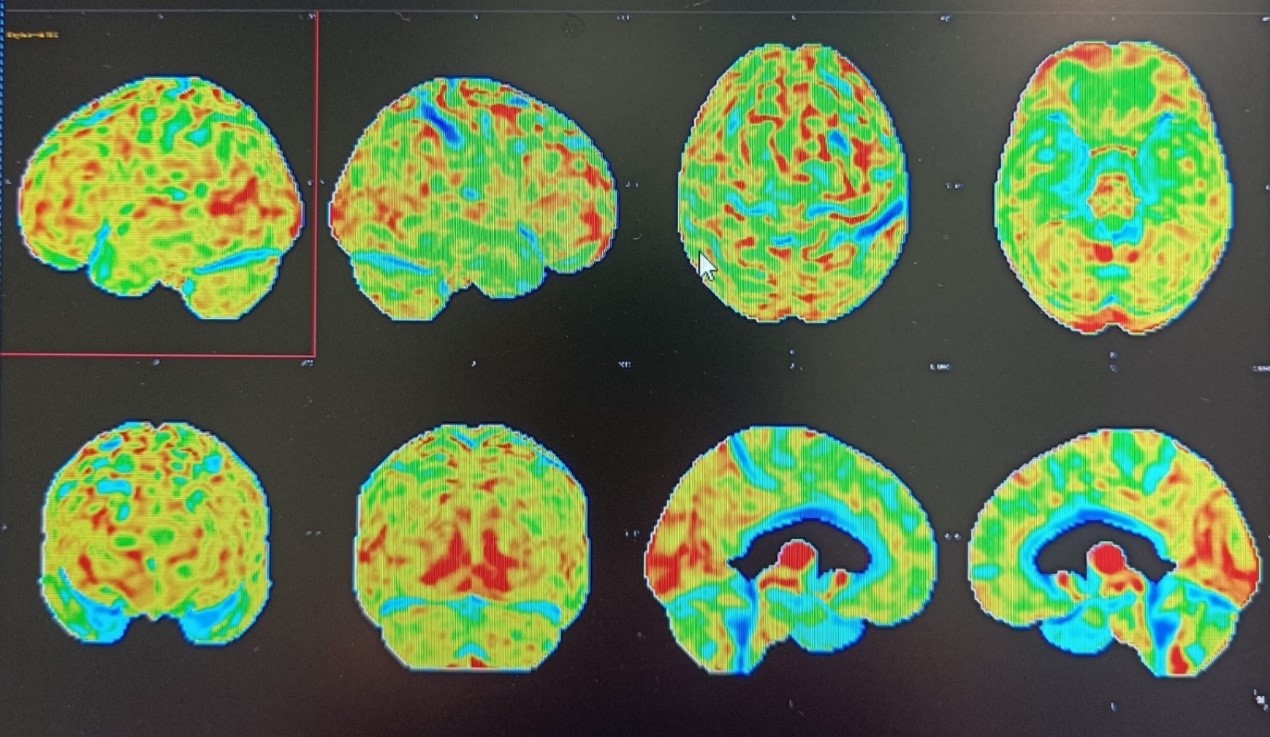

PET αμυλοειδούς

Αποτελεί μια καινοτόμο, μη επεμβατική, απεικονιστική τεχνική για την πρώιμη και ακριβή διάγνωση της νόσου Αλτσχάιμερ με εξαιρετικά υψηλή ευαισθησία και ειδικότητα.

ΤΜΗΜΑ PET-CT ΝΟΣΟΚΟΜΕΙΟΥ ΥΓΕΙΑ